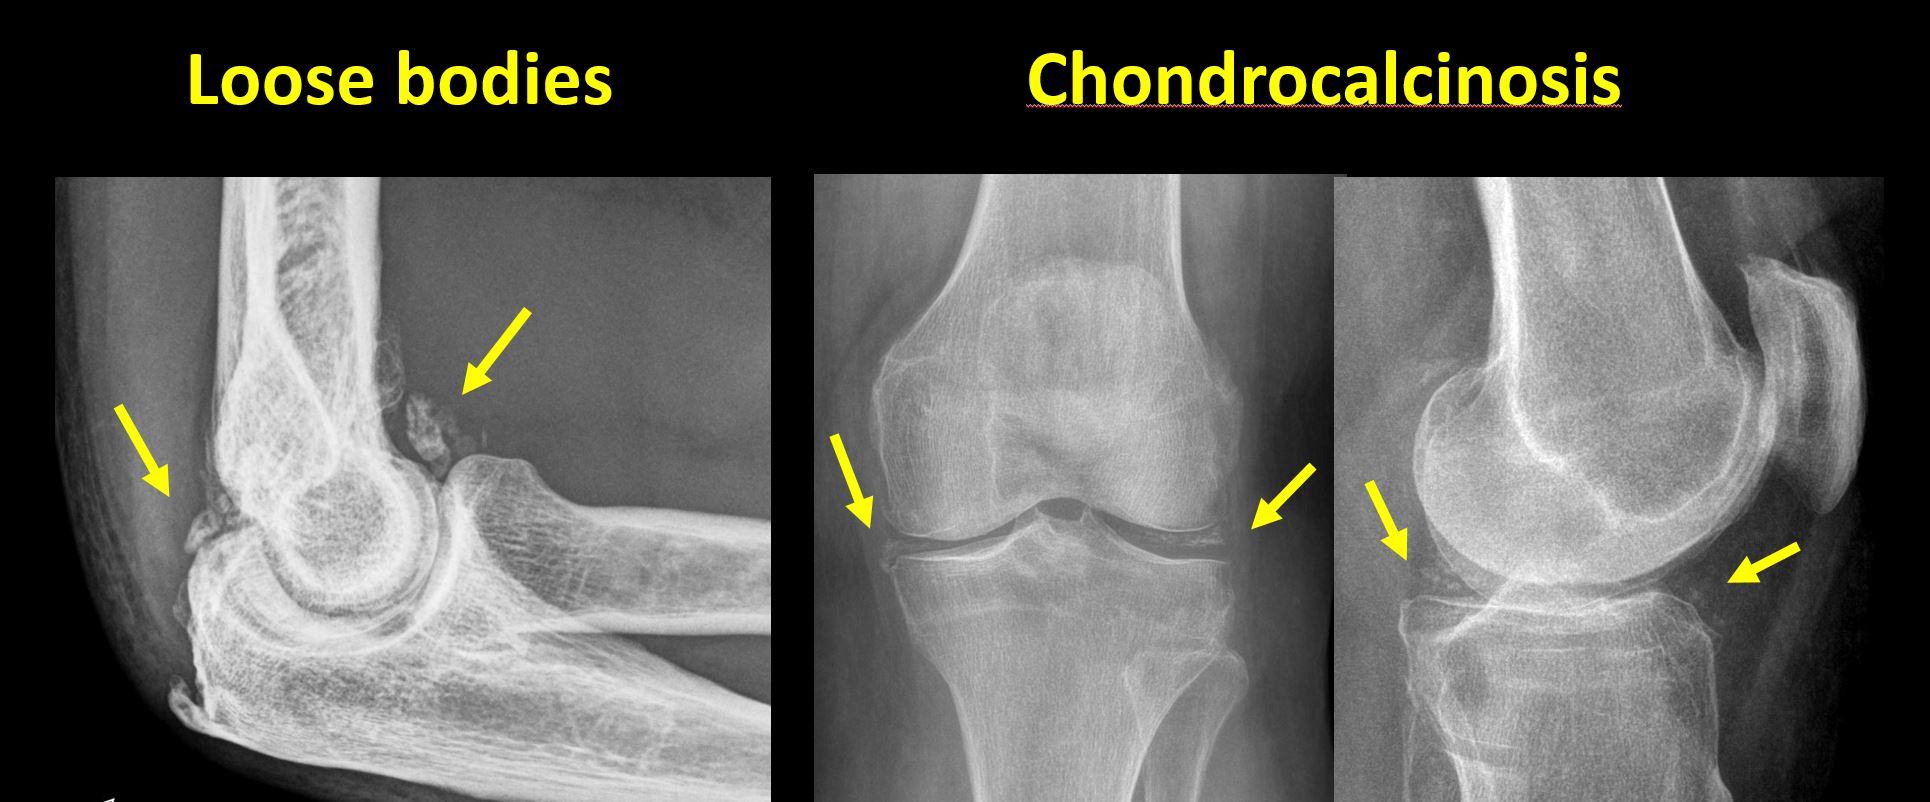

There is an intra-articular loose body or chondrocalcinosis. |

No | NA |